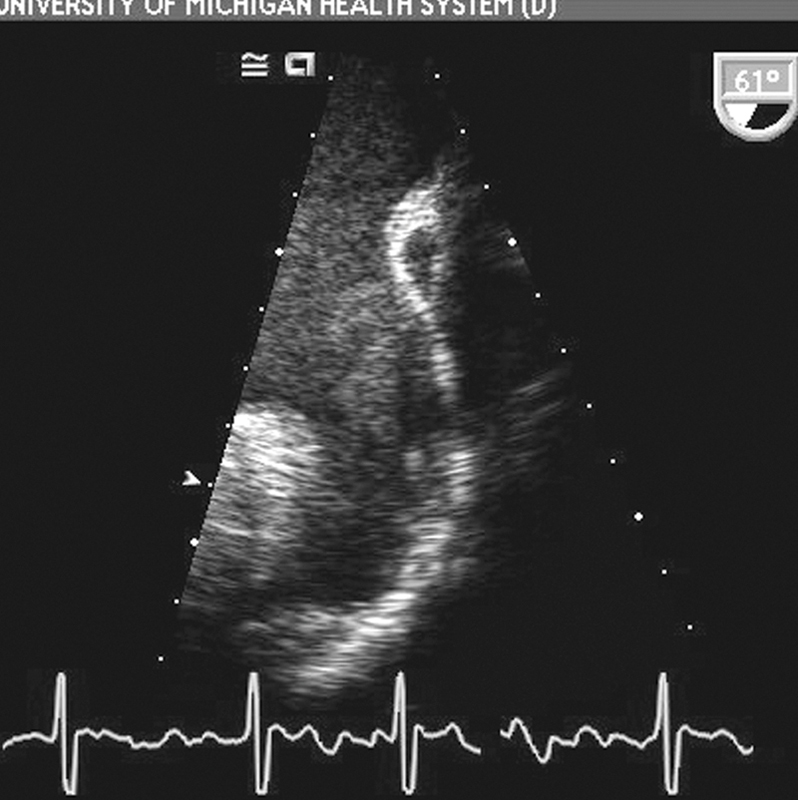

فحوصات تشخيصية لبعض امراض القلب والشرايين التاجية